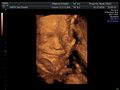

Tinchen´s Krümelchen 13. +1 (14. SSW)

13.10.2010

Krümel ist jetzt 8,7 cm groß. Das Herz hat ganz fleißig geschlagen. Und eine gratis Turnstunde gab es auch noch zu sehen.